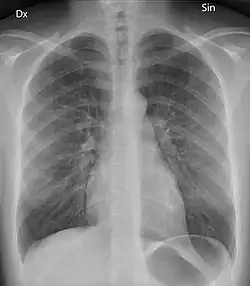

![]() Una radiografía de tórax posteroanterior normal. Dx y Sin significan "derecha" e "izquierda" respectivamente. | ||

Una radiografía de tórax es una radiografía de proyección del tórax que se utiliza para diagnosticar las condiciones que afectan al tórax, su contenido y las estructuras cercanas (pulmones, el corazón,etc ). Las radiografías de tórax son la imagen más común que se toma en medicina.